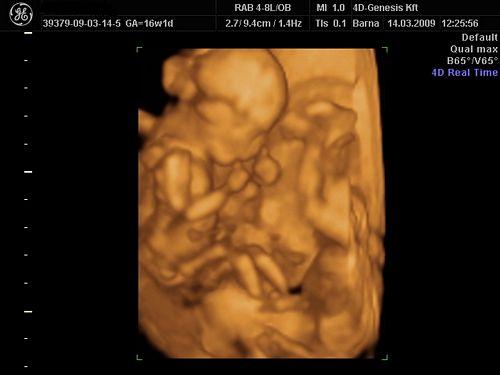

Amit adtak a 4d genesisben képet vagy cd-t, amin a képek vannak nézd meg hogy mekkora amérete. ha nagyobb az előbb megadottnál akkor kicsinyíteni kell.